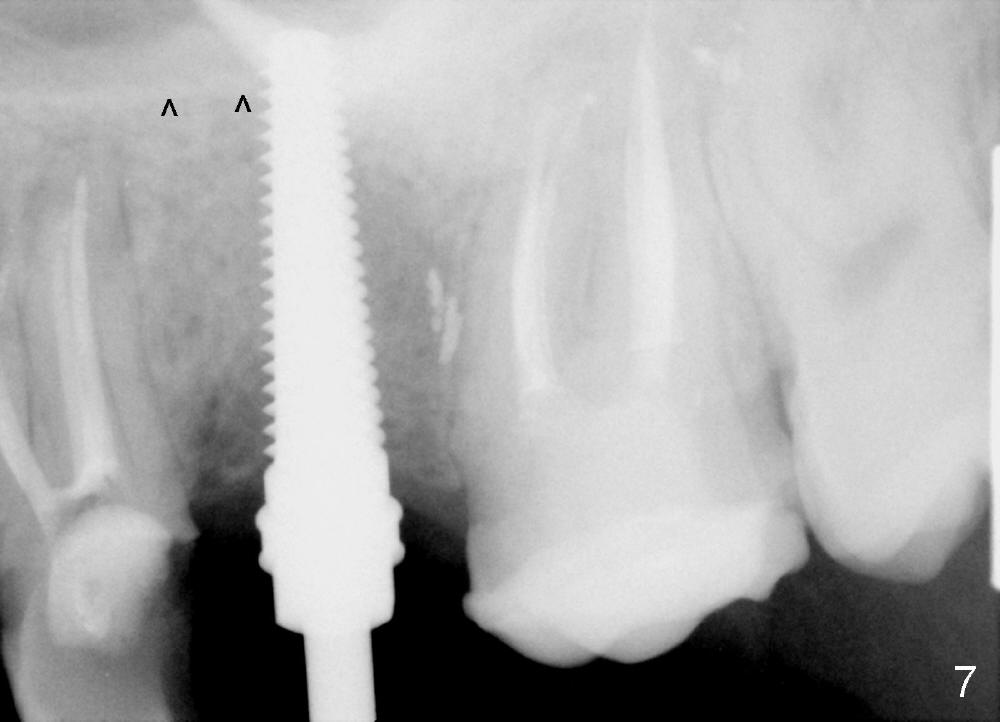

The socket looks empty two months post-extraction (Fig.4 S). Bone appears to re-grow in the socket 9 months after extraction (Fig.5 S), but the buccal plate is severely atrophic and concave (Fig.6 arrowheads). When an incision is made, the socket feels soft. Osteotomy is created by bone expansion (round tapered osteotomes (RT) 2,3,4 mm). Drilling is done once, using 3.5x17 mm tapered drill when the larger RTs meet resistance near the sinus floor. Tapered taps are used to continue to expand the osteotomy (4.5 (Fig.7), 5.0 and 6.0x20 at the depth of 17 mm). Finally 6.0x17 mm implant is placed with insertion torque more than 60 Ncm (Fig.8). The buccal plate is less concave with bone expansion and implantation (Fig.9 arrowheads). Without immediate implant, bone resorbs quick, which makes delayed implantation difficult.